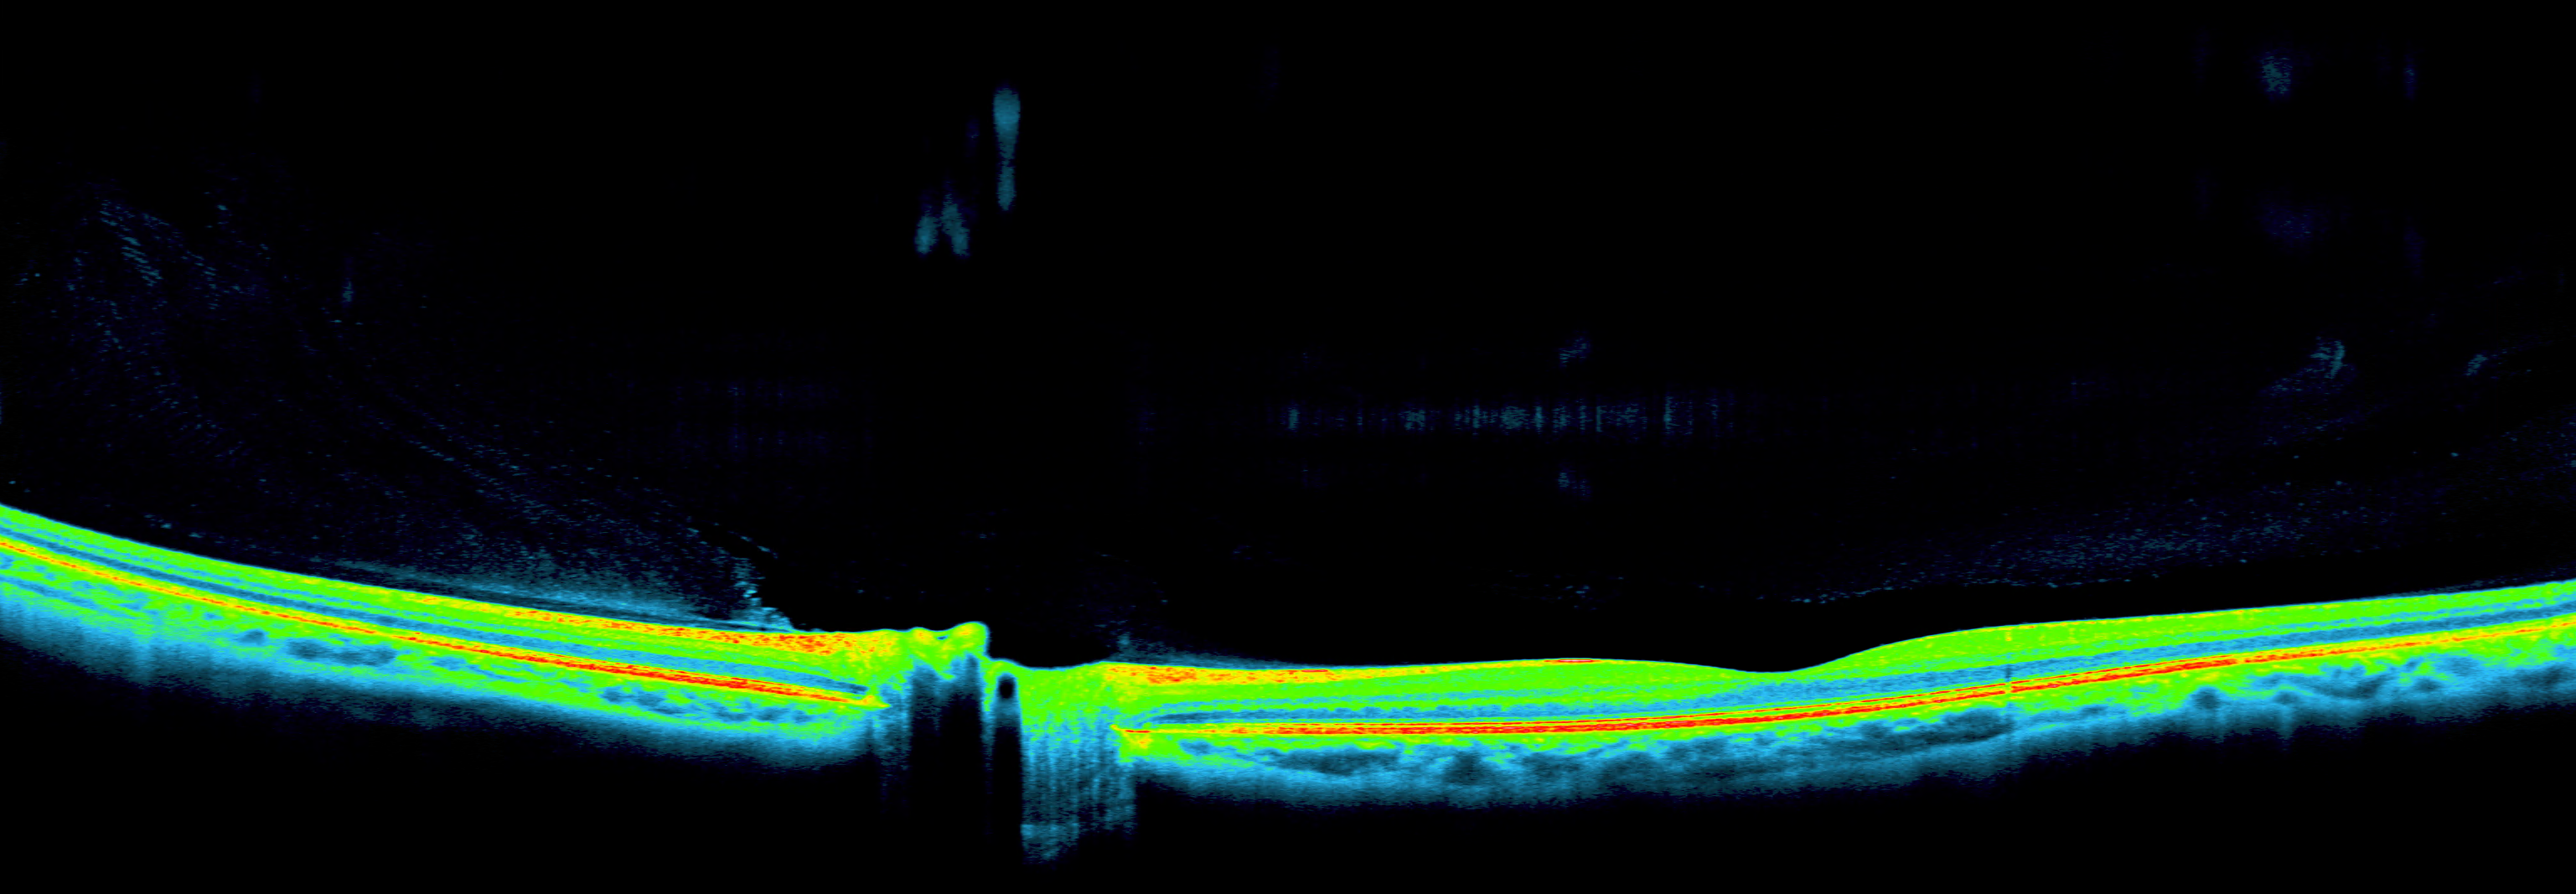

OCT Longitudinal Spine

OCT pipeline multivendor → DICOM SR

Retinal AI over Gass (OCT segmentation)